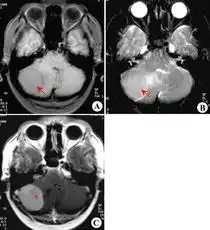

一看就有大病的头像脑瘤 描述: 一看就有大病的头像脑瘤 创立日期: 2025-05-22 00:07:12 图片数量: 0 pics 浏览量: 通过脑室内注射cart首次消灭致命脑瘤的研究团队,这次盯上了乳腺癌脑转移 最新科技自动掏耳神器,360无死角,让你爽翻天 右乙状窦区脑膜瘤纤维型mri病例图片影像诊断影像园 犬脑膜瘤的综述 6岁儿童一口气读不了白日依山尽不是贵人语迟是脑肿瘤 中华医学网 腹腔大病灶,快来围观有病理影像医学和核医学讨论版 嗅沟脑膜瘤olfactorymeningiomamrict病例图片影像诊断分析 美科学家研发读心程序可将大脑想法转换成语音 口苦可能是大病预警,一定要重视 农夫捡到一大堆子弹吓得够呛,清洗后发现透亮鉴定后大喜 类别: 2025头像大全